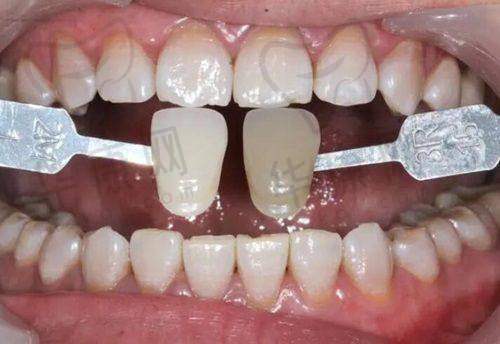

现在,我的种植牙已经用了一段时间了,成效真的超出了我的预期。外观上和真牙几乎没有区别,吃东西的时候也特别给力,啃排骨都没问题。我真的特别感谢北海柏乐口腔的刘鹏医生和他的团队,是他们不错的技术和贴心的服务让我重新拥有了健康的牙齿。如果你也有牙齿缺失的困扰,不妨来北海柏乐口腔找刘鹏医生试试即刻种植牙。